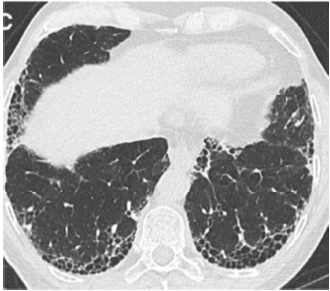

Paciente com 75 anos de idade, masculino, procedente de Minas Gerais, é encaminhado da atenção básica, devido a um quadro de tosse crônica seca (início há alguns anos) associado a dispneia que vem piorando (atualmente mMRC 3).

No interrogatório sintomatológico, o paciente relata também apresentar sintomas de refluxo com certa frequência. Ele nega sintomas de vias aéreas superiores, chiado torácico, febre, perda ponderal e dores articulares.

Antecedentes pessoais: o paciente relata ter diabetes e hipertensão arterial sistêmica, com uso regular de metformina e valsartana, nega história de infecções respiratórias prévias recorrentes e doenças reumatológicas diagnosticadas. O paciente afirma que nunca fumou.

História ocupacional/exposições: o paciente relata que trabalhou a vida toda em escritório, um ambiente que ele diz ser arejado e sem poeira, e também nega ter contato com aves, mofo e travesseiro de pena.

No exame físico: verifica-se bom estado geral do paciente, anictérico, orientado em tempo e espaço, com frequência respiratória de 28 irpm, frequência cardíaca de 99 bpm, pressão arterial 130 × 80 mmHg e saturação de oxigênio em ar ambiente de 89%.

Aparelho respiratório: sons respiratórios presentes bilaterais, com crepitações teleinspiratórias em regiões infraescapulares e axilares posteriores, sem uso de musculatura acessória.

Aparelho cardiovascular: ritmo cardíaco regular, hiperfonese de componente P2 em foco pulmonar, sem sopros.

Extremidades: discreto edema de membros inferiores bilateral, sem sinais de trombose, tempo de enchimento regular de 2 segundos e presença de baqueteamento digital.

O paciente traz uma tomografia prévia solicitada pelo médico de família e representada nas imagens a seguir.

American Journal of Respiratory and Critical Care Medicine. Volume 198 Number 5 September 1 2018 (com adaptações).

Considerando a principal hipótese diagnóstica para o caso clínico hipotético apresentado anteriormente, julgue os itens a seguir.

I Geralmente a doença em questão ocorre em pacientes mais velhos, entre a sexta e a sétima década de vida. Frequentemente pacientes com esse diagnóstico apresentam como manifestação inicial uma exacerbação aguda.

II Os critérios diagnósticos são baseados na exclusão de outras causas de doença pulmonar, associados a padrão tomográfico específico ou combinações entre padrões tomográficos e histopatológicos.

III A broncoscopia pode auxiliar no diagnóstico. O esperado é que seja encontrada redução dos neutrófilos e(ou) linfocitose.

IV A reunião multidisciplinar (pneumologista, radiologista, cirurgião torácico e patologista), pode ajudar nos casos em que a tomografia sugere diagnóstico alternativo.

V Alguns diagnósticos diferenciais para o quadro descrito acima são: pneumonite de hipersensibilidade, doenças reumatológicas cursando com pneumopatia e toxicidade a drogas.

Estão certos apenas os itens